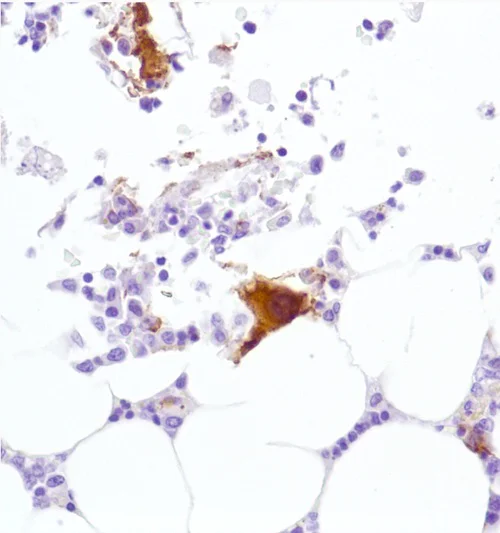

Immunohistochemistry (Formalin/PFA-fixed paraffin-embedded sections) - Anti-CD42b antibody [SP219] (AB183345)

Immunohistochemistry (Formalin/PFA-fixed paraffin-embedded sections) analysis of Human bone marrow tissue sections labeling CD42b with ab183345 at 1/100 dilution (1.94 μg/ml). Heat mediated antigen retrieval with citrate buffer (pH 6.0, epitope retrieval solution 1) for 10mins. Rabbit specific IHC polymer detection kit HRP/DAB (ab209101) was used as the secondary antibody. Hematoxylin was used as a counterstain. Positive staining on the megakaryocytes in the human bone marrow, performed on a Leica Biosystems BOND™ RX instrument.

The section was incubated with ab183345 for 10 mins at room temperature.